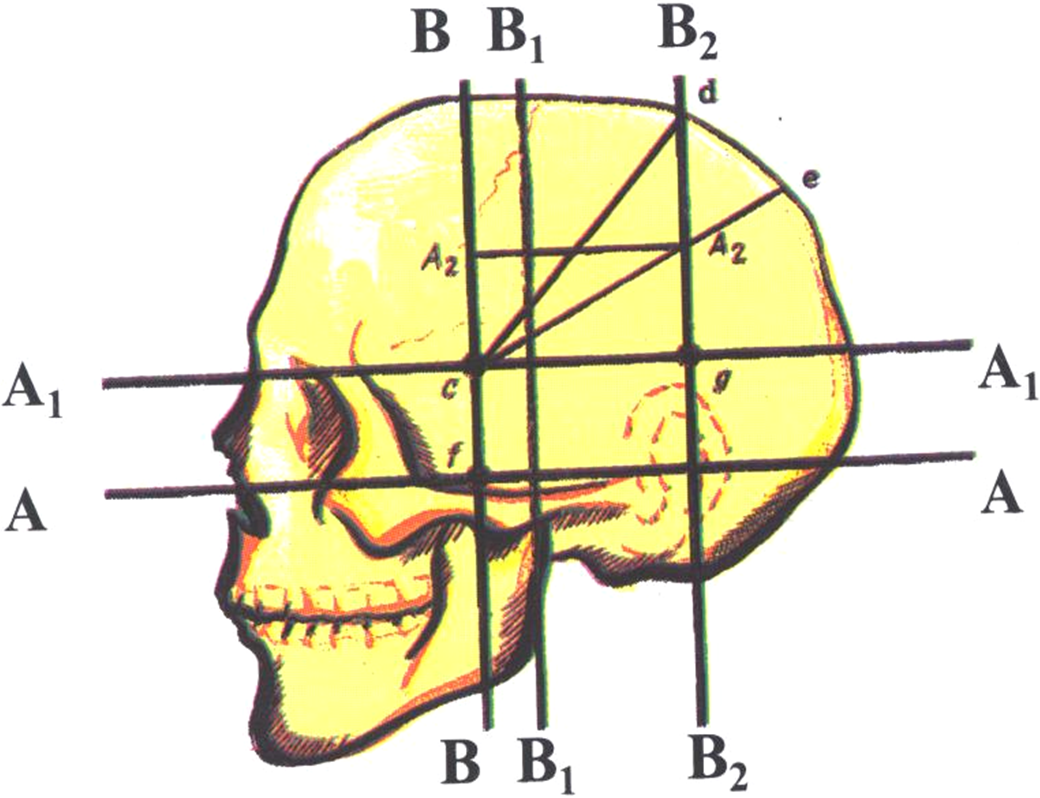

Анатомические изображения срединной сагиттальной линии черепа